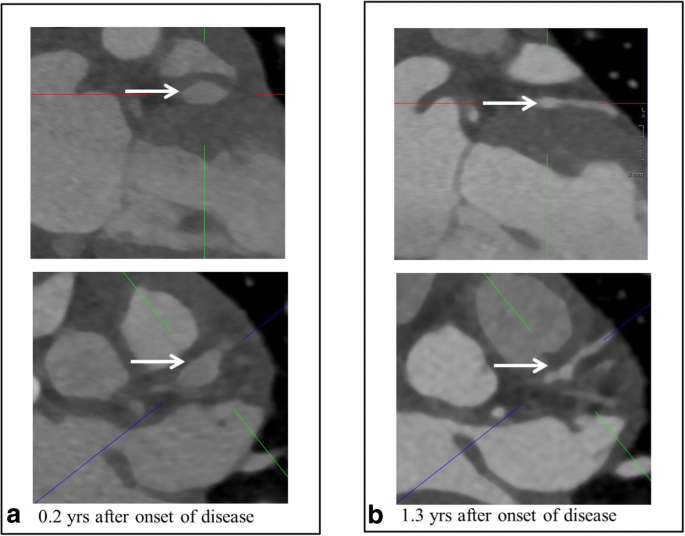

The imaging in our patients was categorized according to the phase at the time of cCTA. The “dynamic phase” includes the first two years after the onset of disease in which the largest changes in Z scores can still occur; an example of this active remodeling has been depicted in Fig. 2, or thereafter in which secondary complications occur: the “static phase” (Fig. 3). The static phase is a stable phase with a view to CAAs.

Fig. 2

figure 2

Remodeling of the LAD (in a single patient) performed with the third-generation dual-source CT scanner. a Significant aneurysms in the LAD (5.3-mm diameter, Z score 16.28). b Remodeling of the LAD in the dynamic phase (2.8-mm diameter, Z score 4.23)